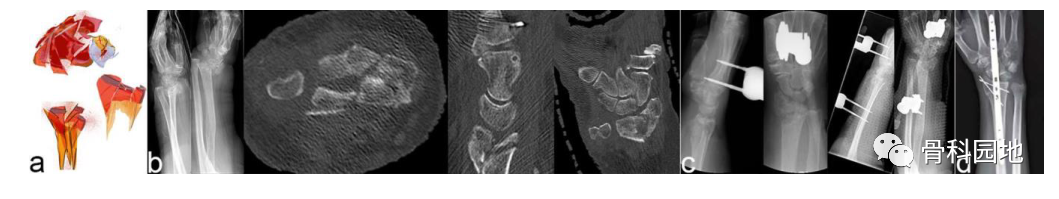

2、三部分骨折

注:这种骨折是桡骨、掌尺骨和背尺骨骨折块的组合(见图 a、b)。每个骨块都是同等重要的关键片段。尽管它们与轴没有连接,但修复对于保持第一腕骨相对于桡骨和尺骨的稳定性至关重要。